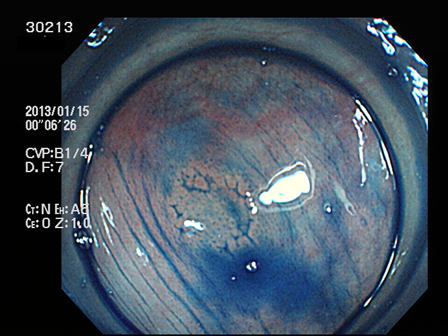

上記100名より抽出した平坦・陥凹型腺腫(=癌化の危険が高いが見落としやすい病変)の内視鏡写真